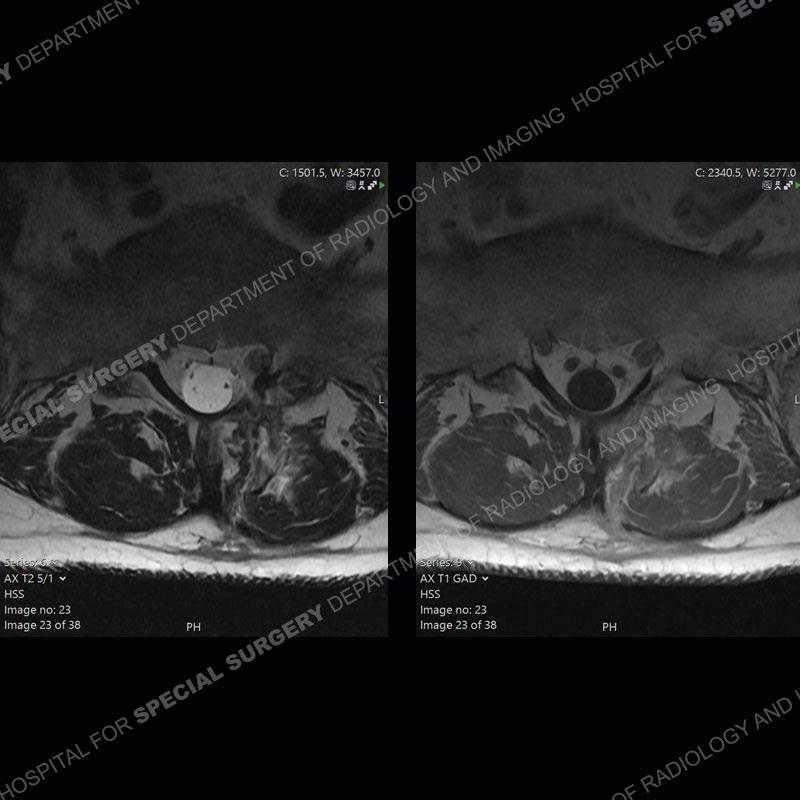

Post operative changes are seen on the left side at L5-S1 where there is near complete removal of the left sided L5 lamina, partial resection of the left L5-S1 facet joint, and resection of the left sided ligamentum flavum. In the anterolateral epidural space about the subarticular recess is a mass that demonstrates similar T1 and T2 signal characteristics to the adjacent degenerated disc. There is enhancement about the periphery of the mass, but the majority of this somewhat geographic or polyploid mass demonstrates no enhancement. The mass exerts prominent mass effect on the left S1 axillary sleeve/proximal nerve root. The left S1 nerve root shows enlargement and increased enhancement as compared to the contralateral right side.

Diagnosis: Recurrent Disc Herniation

Not as much of a diagnostic dilemma as some other cases but more so just a very nice example of what can be a difficult assessment at times. The evaluation of granulation tissue/scar/epidural fibrosis vs. disc herniation particularly in the earlier post operative period can be very difficult. Clues that can assist in identifying a disc herniation are a more geographic or polypoid nature to the mass, signal characteristics similar to the adjacent degenerated disc, mass effect upon the thecal sac/adjacent neural structures, and a typical enhancement pattern. As the disc material is avascular, as long as imaging is performed in a relatively rapid fashion after contrast administration (within 20-30 minutes), the granulation tissue around the disc will enhance but the disc material itself will not. If there is a marked delay between contrast administration and imaging, there may be diffusion of contrast into the disc making the assessment very difficult. The marked utility of contrast to help delineate disc vs. scar has led to our institution employing contrast fairly uniformly within the first two years following surgery.

The scar tissue in the setting of prior disc removal will be present in the anterior and anteriorlateral aspect of the epidural space. The signal characteristics can be somewhat variable from slightly more T2 hyperintense earlier on to T2 hypointense as the scar matures. However, the signal does not tend to follow the adjacent degenerated disc. The scar can produce mass effect, but it does not have to do so. In addition, at times the scar may be associated with a retraction of the adjacent thecal sac. Given the vascular nature of the scar there is typically somewhat avid, uniform enhancement which occurs fairly rapidly after contrast administration and begins to diminish within 20 minutes or so. Trying to discern the difference between scar and disc is of paramount importance given the rather poor outcomes associated with resection of scar as compared to disc material.